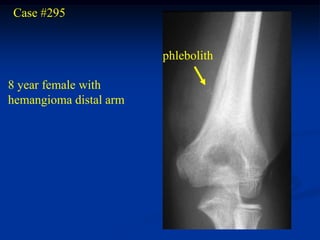

Case #295

phlebolith

8 year female with

hemangioma distal arm

Lateral view

Coronal T-1 MRI   Coronal T-2 MRI

Sagittal T-1 MRI   Sagittal T-2 MRI

Axial T-1 MRI   Axial T-2 MRI

Case #295 phlebolith 8 year female with hemangioma distal arm